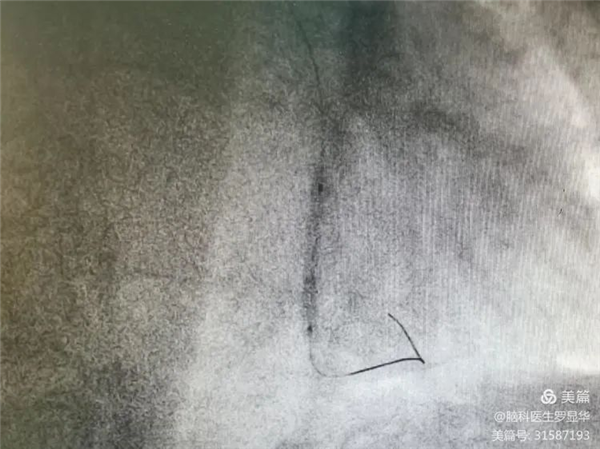

釋放冠脈球擴支架

支架植入后狹窄完全解除